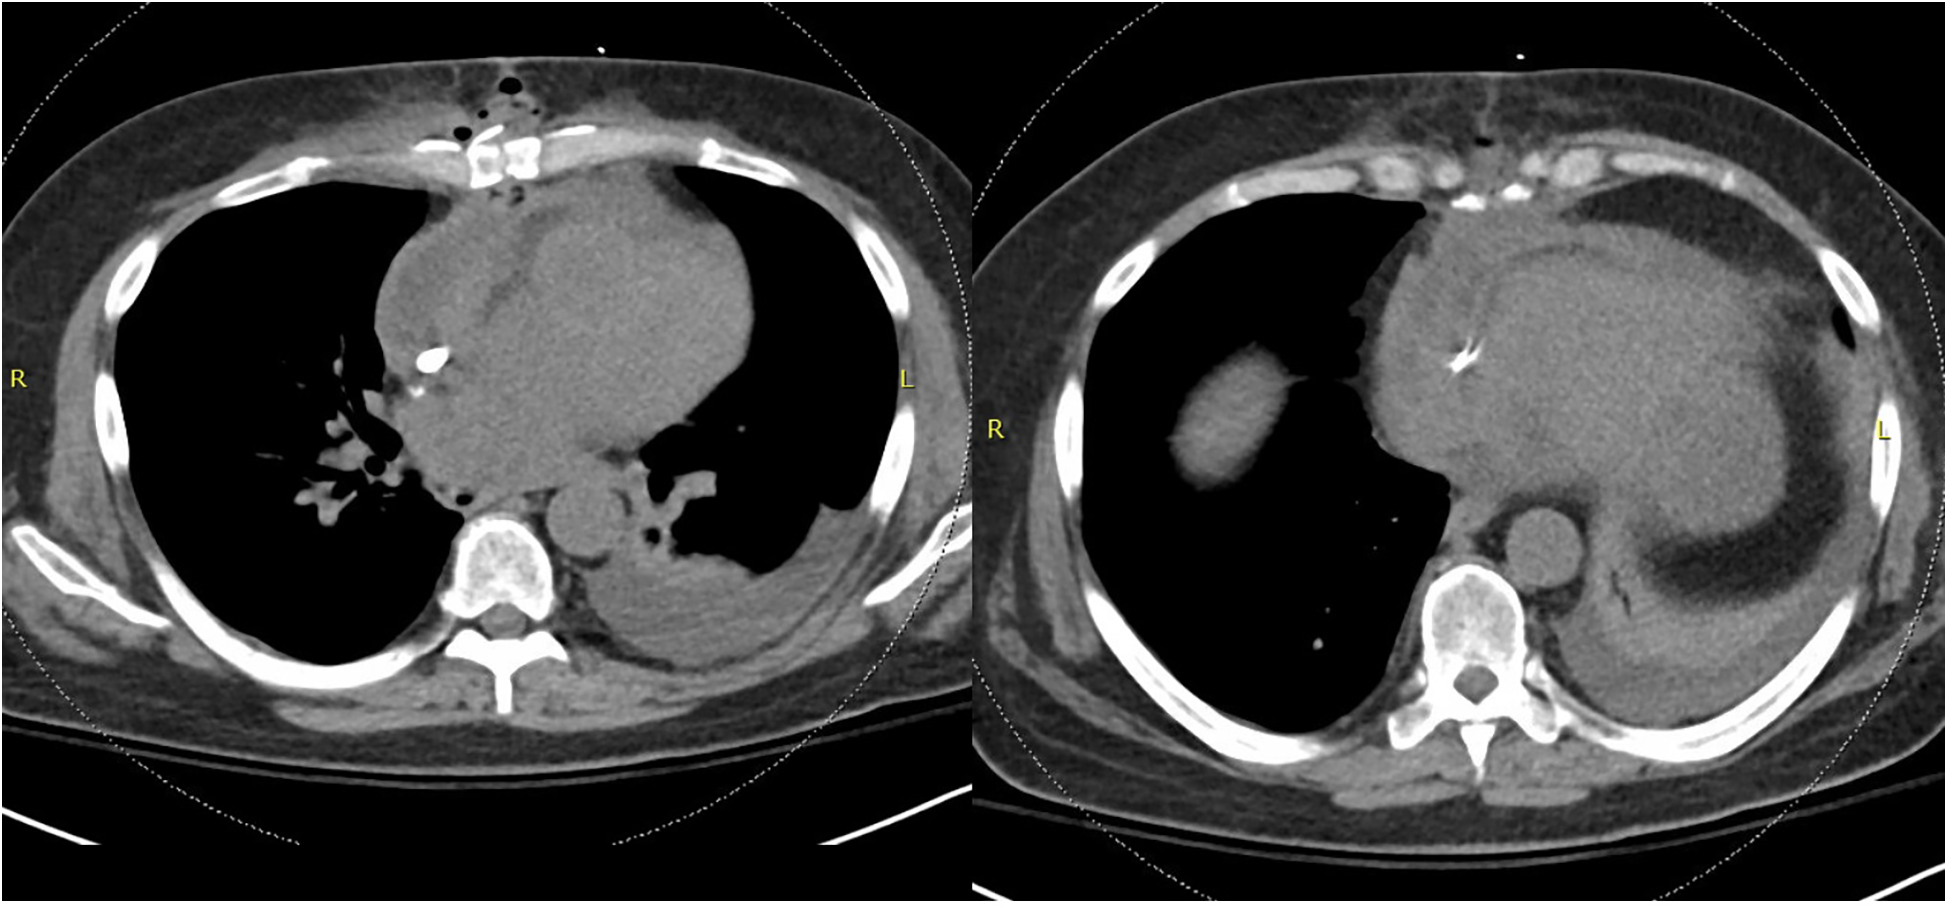

Six days after discharge, the patient was readmitted with nausea, vomiting, and fever. Admission labs were notable for leukocytosis and imaging revealed dehiscence of the chest wall incision with inflammatory changes and gas surrounding the sternotomy concerning for deep sternal wound infection and osteomyelitis (FigureĀ 1). The patient was promptly restarted on IV voriconazole 500ā mg every 12ā h twice as a loading dose followed by 300ā mg every 12ā h for maintenance dosing.

Figure 1

Non-contrasted CT chest demonstrating dehiscence of the chest wall incision with inflammatory changes and gas concerning for deep sternal wound infection.